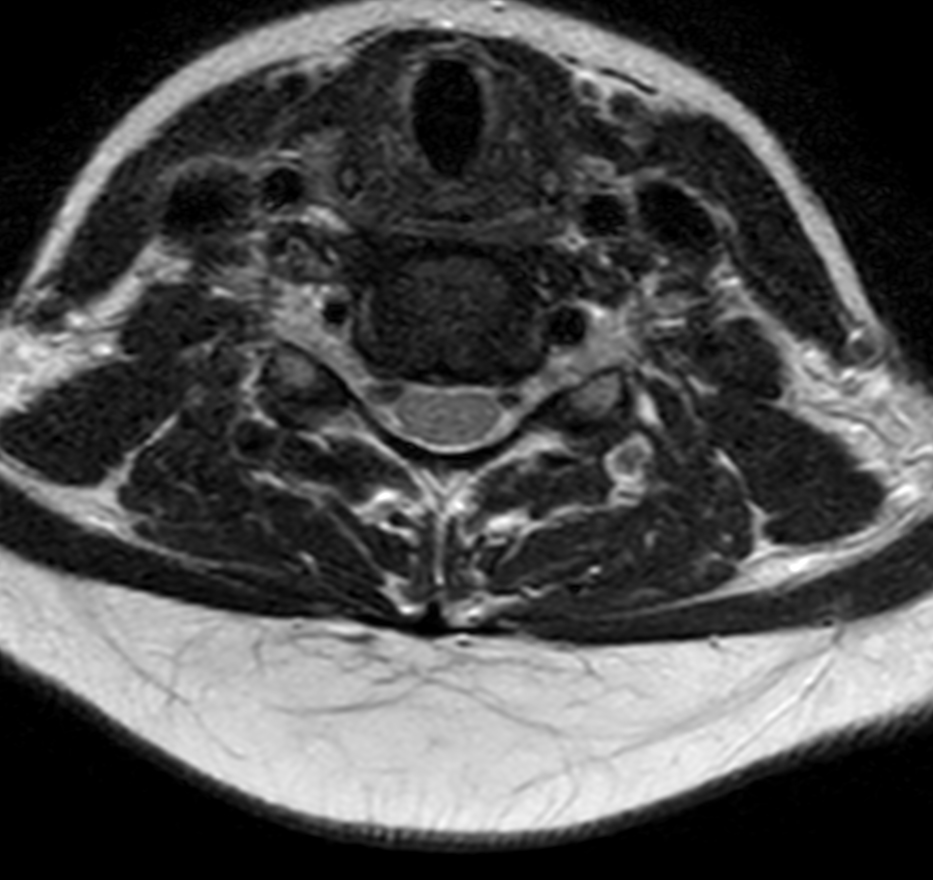

Cervical Spine on BlueSeal magnet

Spital Uster, Switzerland

Axial T2w TSE (small FOV)